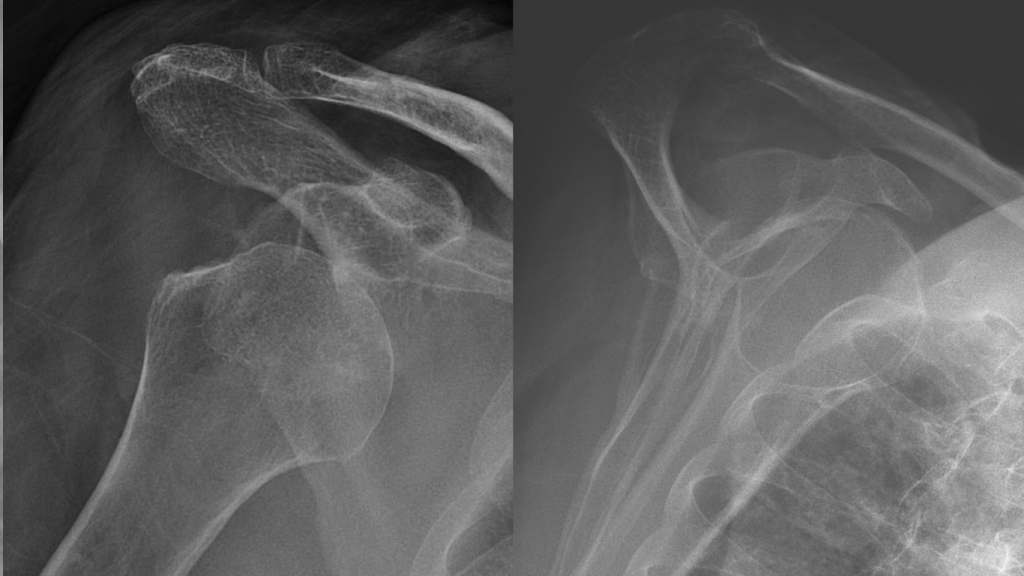

راه های تشخیص در رفتگی کتف چیست؟

تشخیص دررفتگی کتف معمولاً با بررسی علائم بالینی و انجام تصویربرداری پزشکی صورت میگیرد. پزشک ابتدا با مشاهده تغییر شکل ظاهری شانه، بررسی دامنه حرکتی، و ارزیابی درد و تورم، به احتمال دررفتگی پی میبرد. سپس برای تأیید تشخیص، از تصویربرداریهایی مانند رادیوگرافی (X-ray) استفاده میشود تا محل دقیق استخوان و نوع دررفتگی مشخص شود. در موارد پیچیدهتر یا برای بررسی آسیب به بافتهای نرم، ممکن است MRI یا سیتیاسکن نیز تجویز شود. تشخیص دقیق و سریع، نقش مهمی در جلوگیری از آسیبهای ثانویه و انتخاب روش درمان مناسب دارد.